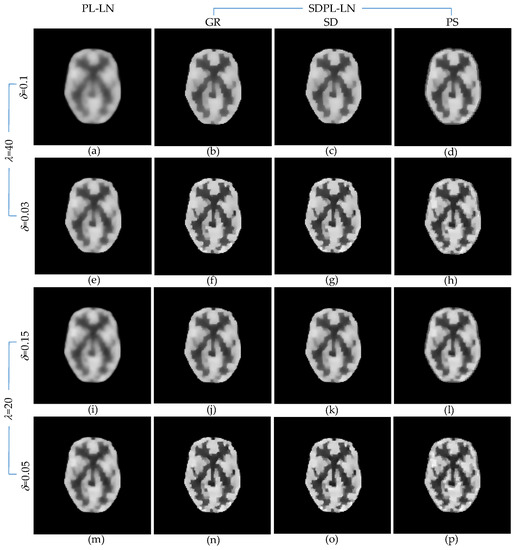

3.1. Numerical Studies Using Digital Phantom

3.2. Qualitative Validation Using Physically Acquired Data

| = 40 = 0.1 | PSNR(dB) | 13.943 | 15.569 | 15.621 | 14.999 |

| SSIM | 0.821 | 0.872 | 0.874 | 0.854 | |

| VIF | 0.404 | 0.540 | 0.547 | 0.531 | |

| MAE | 0.090 | 0.068 | 0.068 | 0.071 | |

| RMSE | 0.201 | 0.167 | 0.166 | 0.178 | |

| MPE | 36.651 | 30.396 | 30.216 | 32.459 | |

| = 40 = 0.03 | PSNR(dB) | 15.475 | 17.133 | 17.232 | 16.856 |

| SSIM | 0.869 | 0.910 | 0.912 | 0.905 | |

| VIF | 0.539 | 0.675 | 0.688 | 0.672 | |

| MAE | 0.069 | 0.051 | 0.050 | 0.052 | |

| RMSE | 0.168 | 0.139 | 0.138 | 0.144 | |

| MPE | 30.728 | 25.387 | 25.101 | 26.210 | |

| = 20 = 0.15 | PSNR(dB) | 14.659 | 16.186 | 16.222 | 15.756 |

| SSIM | 0.843 | 0.887 | 0.887 | 0.876 | |

| VIF | 0.474 | 0.593 | 0.598 | 0.590 | |

| MAE | 0.079 | 0.061 | 0.061 | 0.063 | |

| RMSE | 0.185 | 0.155 | 0.155 | 0.163 | |

| MPE | 33.754 | 28.311 | 28.194 | 29.748 | |

| = 20 = 0.05 | PSNR(dB) | 16.001 | 17.543 | 17.601 | 17.151 |

| SSIM | 0.882 | 0.919 | 0.920 | 0.913 | |

| VIF | 0.587 | 0.720 | 0.730 | 0.706 | |

| MAE | 0.063 | 0.047 | 0.046 | 0.050 | |

| RMSE | 0.159 | 0.133 | 0.132 | 0.139 | |

| MPE | 28.922 | 24.217 | 24.056 | 25.335 | |